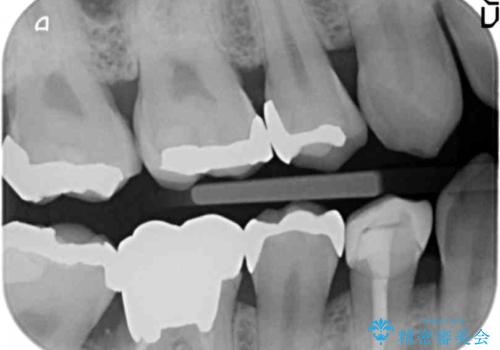

右下7については、遠心の歯の高さがなく、また、同様に歯肉縁下にカリエスがあったため、手術を行い改善しました。

手術はディスタルウェッジとAPFを併せて行なっています。

右下6については、物理的には歯を使うことは可能ですが、残すと悪くなっていくのを避けられないような修復しかできないため、長期的な展望が立たないため抜歯をお勧めしました。